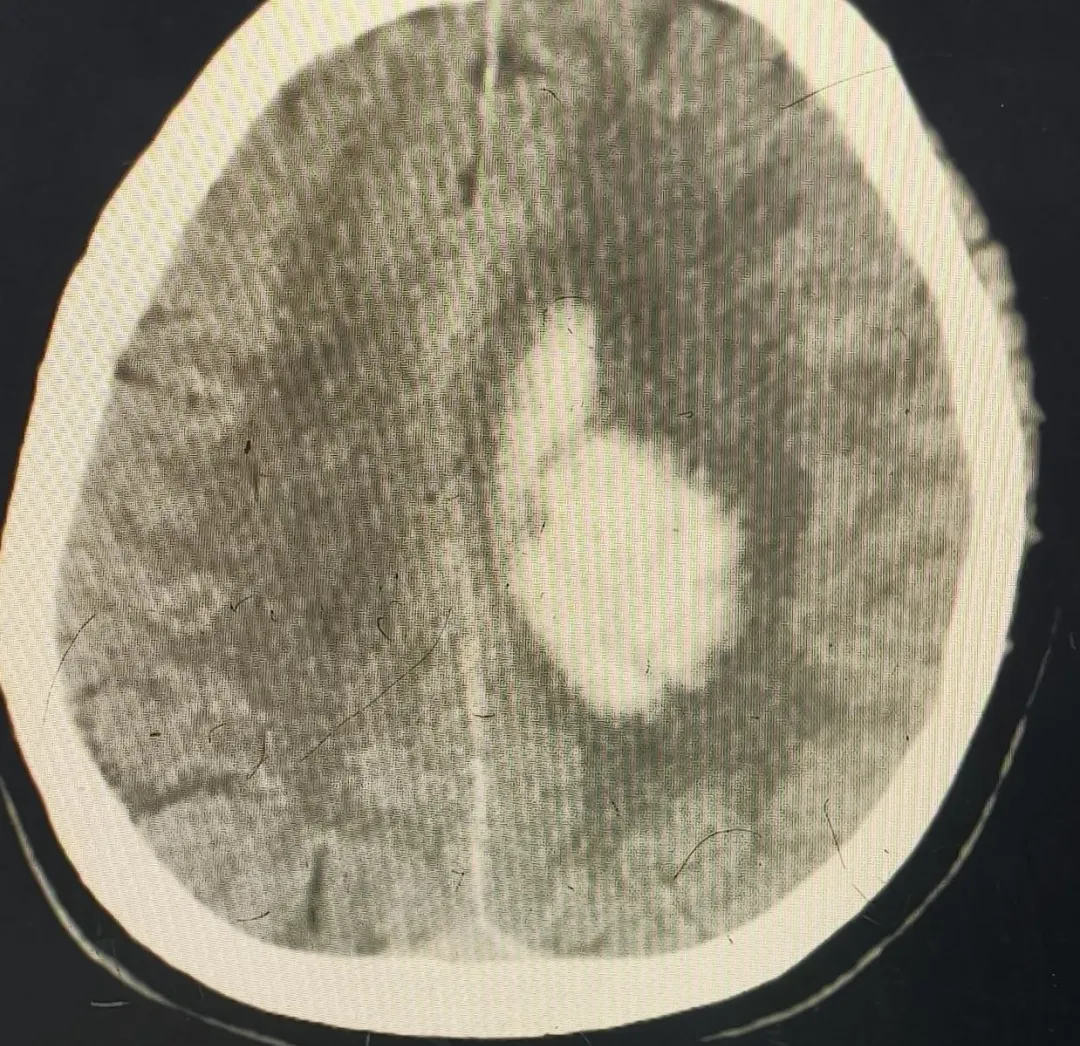

患者王某某(化名),女性,67岁,因“言语不清伴肢体活动障碍1+小时”急诊入院。入院后迅速确诊为“左基底节区-丘脑区脑出血破入脑室、脑疝形成”,病情极其危重。东部新区第二人民医院卒中绿色通道迅速响应,神经外科医生雷长波第一时间为患者实施了“颅内血肿清除+开颅颅内减压术”,成都市第三人民医院神经外科医生李强进行现场手术指导,确保手术精准高效。术后重症监护由市三医院派驻东部新区第二人民医院重症医学专家赵婧莎指导,为生命安全保驾护航。